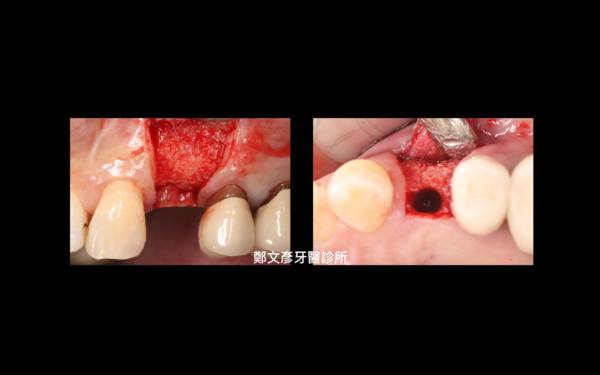

Role of granulation tissue in socket preservation

3. Role of granulation tissue in socket preservation